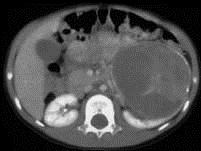

问题 女,54岁,发现腹部包块,请根据所示图像,选择最可能诊断 ( )

选项 A、左侧囊性肾癌 B、左侧肾血管平滑肌脂肪瘤 C、左侧单纯性肾囊肿 D、左侧肾囊肿合并出血 E、左侧肾癌

答案 A